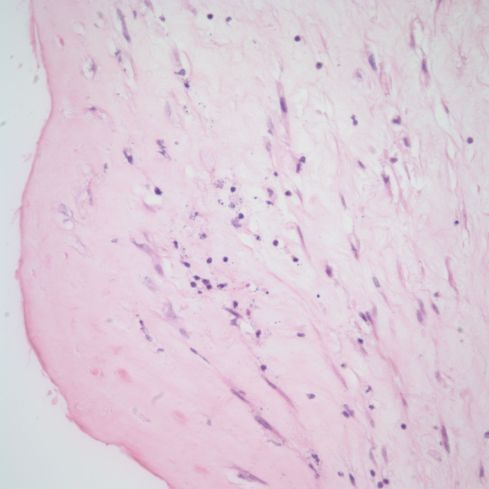

Microscopic features:

The most characteristic feature is the crescent of necrosis, often calcified, that is interposed between the umbilical surface and the vessel walls. Both arteries and vein are usually involved. Commonly there is acute funisitis, often with a gradient of viable neutrophils near the vessel leading to an accumulation of distal necrotic neutrophils (Fig 5).

Fig 5a) The basophilic rim of neutrophils and necrosis at low power.

Fig 5b) A medium power showing the inner basophilic band and an outer band of coagulation necrosis.

Fig 5c) A high power image showing basophilic neutrophils and debris, and then more superficial coagulation necrosis including neutrophils necrosis.